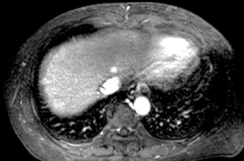

Ø 术前影像学检查

肝 S2 段及肝 S4 段见类圆形 T1WI 低、T2WI-SPAIR/DWI/ADC 高信号,较大者长径

约 10mm,界清。

动脉期